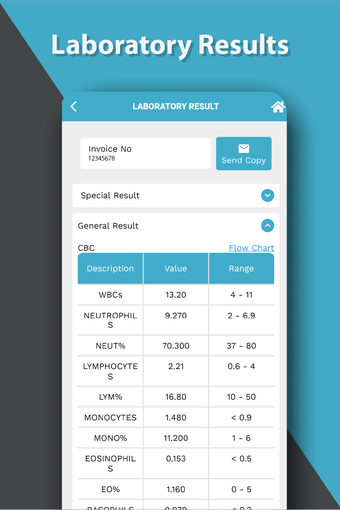

これは、Dr. Sulaiman Al-Habib Medical Services Groupが提供するすべてのサービスにアクセスするのを助ける無料のアプリです。グループの持続的なデジタル変革の重要な部分であり、効率と生産性の向上を重視しています。この新しいアプリは、オンライン医師相談から医療検査や放射線学の報告書まで、グループが提供するすべてのサービスに簡単にアクセスできるようになります。また、あなたと家族の医療記録を閲覧する機会も提供しています。